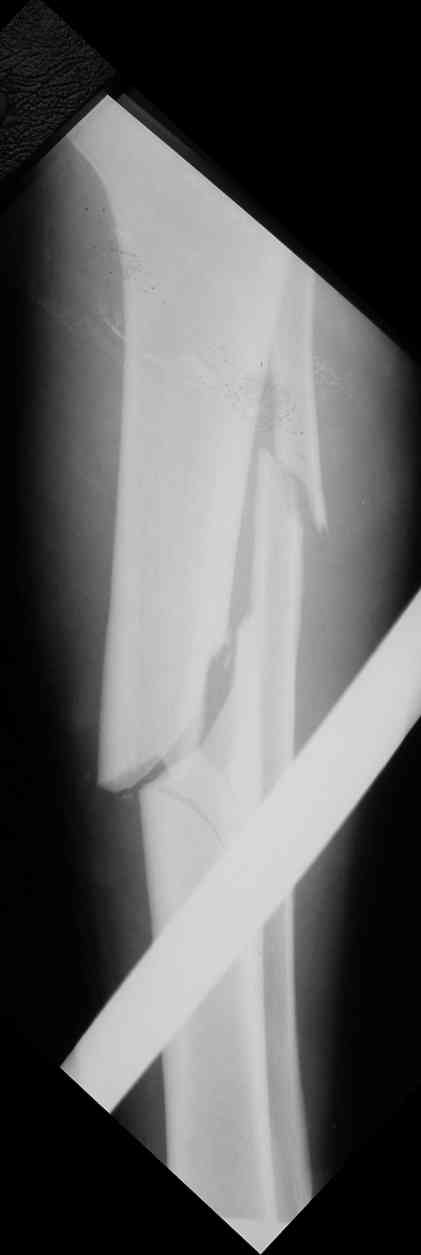

Дорогой Александр. Имею скромный опыт использования системы Fixion при переломах плеча, бедра и тибии. Всего 18 наблюдений с сентября 2006 г. Результаты отличные. Гвоздь индивидуален для каждого медуллярного канала. Легко имплантируется как в узкий, так и в деформированный канал. Это позволяет применять метод интрамедулярного остеосинтеза без ненужных потерь времени операции, флюороскопии и реально снижает крвопотерю и операционный риск. Удаление происходит без проблем. Особенно интересны больные с ипсилатеральными переломами бедра и голени.

В отношении ранней нагрузки при спиральных переломах лучше не торопиться. По данному случаю необходимо достигнуть исчезновения щели между штифтом и внутреним кортексом по Rg. А так картинка прекрасная - и длина сегмента и репозиция. Можно поздравить, коллега!